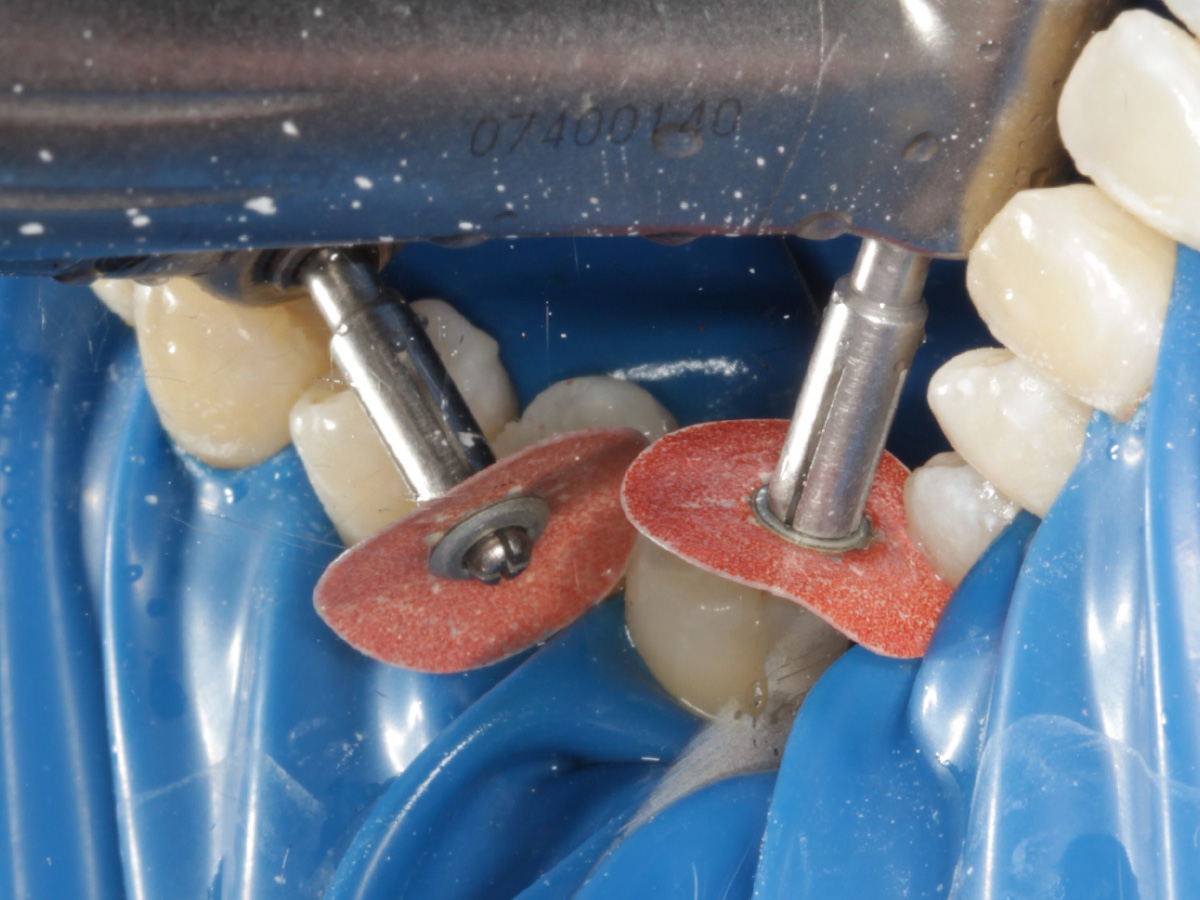

Abbildung 5

Defektdarstellung

Abbildung 6

Kariesexcavation pulpennah mit Kunststoffrosenbohrer